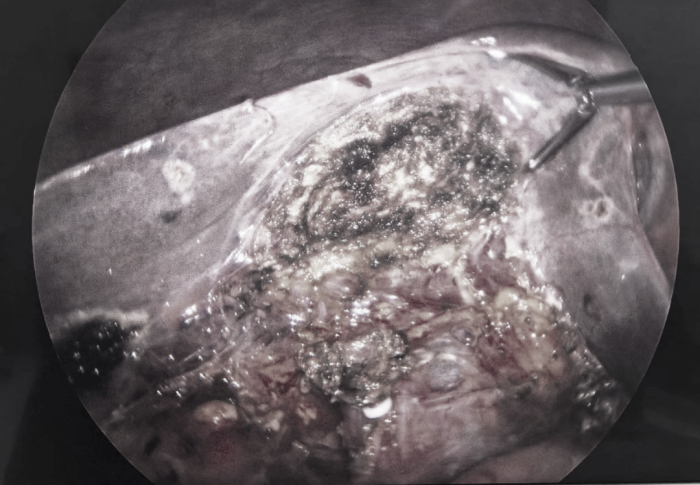

该病人因“反复上腹部疼痛1月余”慕名来到我院,入院后随即进行常规抽血等术前检查,诊断“胆囊结石伴胆囊炎,胆囊化脓坏疽”,当日下午给予安排超微创器械钳辅助单孔腹腔镜胆囊切除,术中见胆囊颈部约1cm结石嵌顿,胆囊极度肿胀,表面脓苔粘附,胆囊壁缺血部分坏死,胆囊内大量无色透明胆汁,切开胆囊后囊内胆汁喷射出来,常规分离胆囊管及胆囊动脉并夹壁,将胆囊从胆囊窝内切取下来,仔细检查创面确认无出血,取下腹壁手术设备,美容缝合腹壁切口。术后2小时开始饮水,4小时后进食稀饭并逐步活动。第二天上午患者几乎没有任何不适并安排出院。